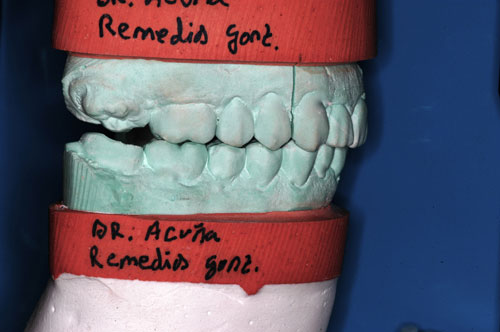

ESTUDIO ESTÁTICO DE LOS MODELOS PREVIOS A LA PRIMERA REHABILITACIÓN APORTADOS POR LA ENFERMA:Modelos Color Blanco

B- ESTUDIO ESTÁTICO DE LOS MODELOS PREVIOS A LA 1ª REHABILITACIÓN APORTADOS POR LA ENFERMA: (La situación oclusal que la enferma tenía antes de que la tocara un dentista (MODELOS COLOR BLANCO)

ESTUDIO ESTÁTICO Y CINEMÁTICO DE LA OCLUSIÓN PRESENTE: Modelos Color Verde

Se realiza un montaje en articulador semi ajustable, mediante la técnica de arco facial convencional para el maxilar superior, y mediante relajación con Laminillas de Long para el inferior. No satisfechos de la certeza del primer montaje, construimos en el un Jig de Lucia que dejamos toda una noche en boca para remontar el inferior al día siguiente a primera hora.

Diferencias entre ambos modelos:

A nivel de segundos molares= 4 mm +

A nivel de primeros molares= 3,50 mm +

A nivel de incisivo central=5,50 mm +

Luego de observar detenidamente el aumento de altura entre los primeros y los segundos modelos, observamos un detalle que de haberlo visto en primer término, nos habría facilitado enormemente el diagnóstico :

Antes de la 1ª intervención, los segundos molares superior e inferior derechos tocaban.